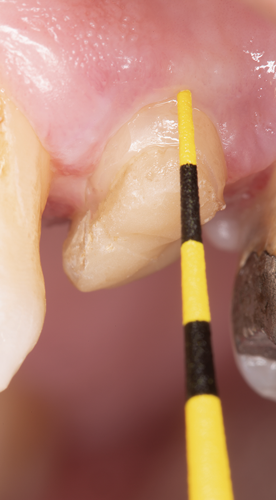

After polymerization and removal of the stopper, the fiber post was cut with a diamond bur to the predetermined length (Figure 17). It should be noted that the clinician should never use a serrated instrument or shears to cut the post to avoid damaging the integrity of the post. The remaining sound tooth structure (ferrule) was etched for 15 seconds with a 37.5% phosphoric acid semigel, rinsed for 5 seconds, and air-dried (Figure 18). With the use of a sable brush, silane was then applied to the coronal portion of the fiber post and existing composite material and air-dried. A universal adhesive was applied to the tooth structure, existing composite material, and fiber post and allowed to dwell for 10 seconds, then air-dried and light-cured (Figure 19).

Fig 18. The remaining sound tooth structure (ferrule) was etched for 15 seconds with a 37.5% phosphoric acid semigel, rinsed for 5 seconds, and air-dried.

Figure 18